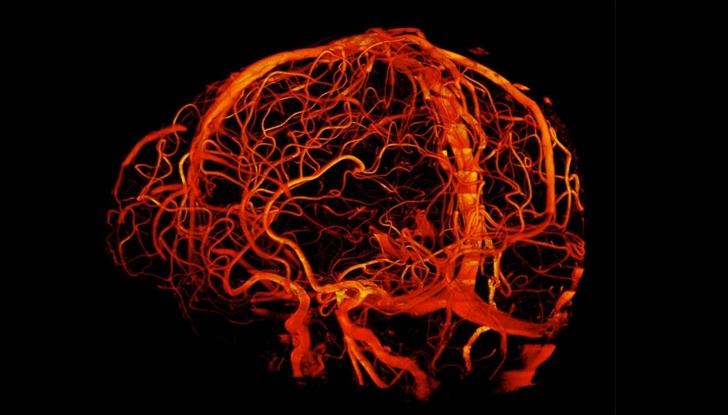

7. Знімок кровоносних судин мозку, зроблений з допомогою потужного томографа в 7 тесла

А в Китаї вже розробили медичний томограф зі значенням магнітної індукції 14 тесла, який може побачити роботу думки. Апарат з таким магнітом чутливий до електронного поля нейронів мозку. Правда, він поки не схвалений для використання на людях.